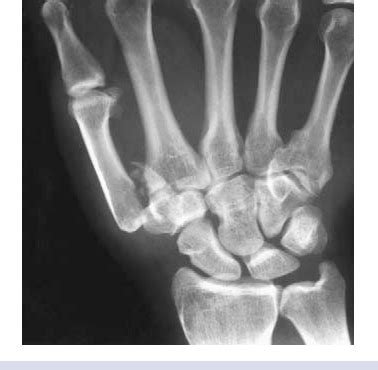

Figure 9 from Injuries of the fingers and thumb in the ...

Figure 9 from Injuries of the fingers and thumb in the ... from ai2-s2-public.s3.amazonaws.com

Avulsion of the flexor digitorum profundus (fdp) tendon from the base of the distal phalanx. In each finger there are two flexor tendons that contribute to the hallmark of the injury is the sudden inability to bend the tip of the injured finger. This usually happens when an athlete grabbing an the injury is typically caused by forceful passive extension while the flexor digitorum profundus muscle is contracting. Jersey finger is the colloquial term for tearing of the tendon that bends the tip of the finger. A zone i flexor tendon injury. Jersey finger injury refers to the damage done to the tip of the ring finger when an athlete grabs the shirt (jersey) of another the same mechanism takes place: Extensor tendon injury at dip (mallet finger). During grip ring fingertip is 5 mm more prominent than other digits in ~90% of patients.

A person who suffers a jersey finger injury in which the fdp tendon is completely ruptured cannot flex the affected digit at the dip joint without assistance. Typically, an athlete will sustain a jersey finger injury while. Mechanism of injury—injury occurs when a flexed dip joint is forcefully hyperextended and the fdp tendon ruptures at its weakest point, which is the insertion site (figure 35.2). The term jersey finger is derived from the classic. Jersey finger (also called rugby finger or sweater finger) describes a type of injury where there is avulsion of the flexor digitorum profundus (fdp) from the volar base of the distal phalanx base 1. This injury got the name jersey finger because rugby players would get their fingers caught in an opponents jersey while trying to tackle them and the pull of the jersey on the finger would cause this injury. Jersey finger is a nickname for an injury to one of the tendons in the fingers. Despite its small size, it may require surgery a jersey finger is an injury to one of the finger tendons.